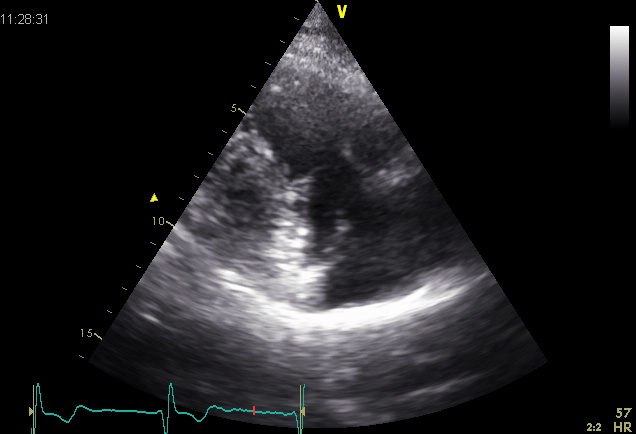

File:Plax TV02.jpg

Plax_TV02.jpg (636 × 434 pixels, file size: 50 KB, MIME type: image/jpeg)

| current | 02:07, 13 December 2013 | 636 × 434 (50 KB) | Nilofer (talk | contribs) |